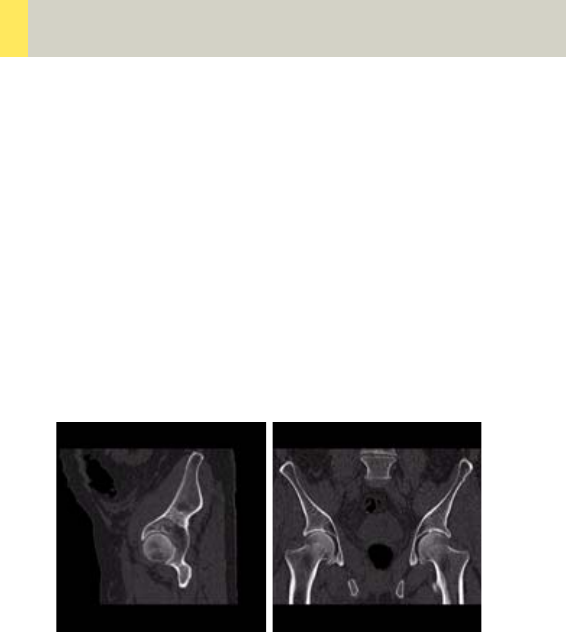

Pelvis 314

•Overview 314

- General Hints 316

- Body Kernels 317

•Scan Protocols 318

- Pelvis 318

- PelvisVol 322

- Hip 324

- HipVol 328

- SI_Joints 330